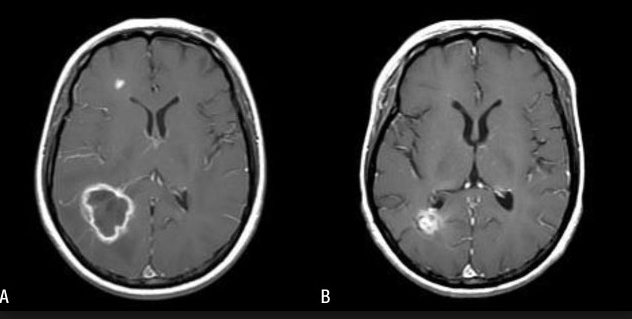

scarecrow with spots at kidney, heart, head black spot with ring: Renal failure

Endocarditis

Ring-enhancing brain lesion (seizures, focal neuro deficits, with symptoms)